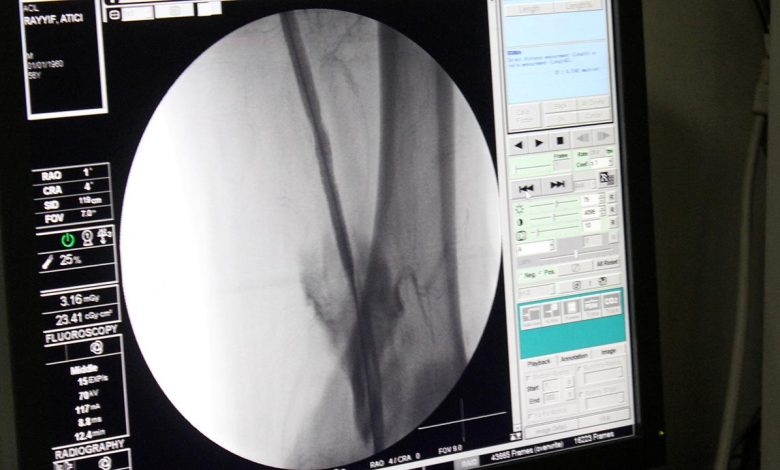

Nihai tasarımlarının, bir prostetik venöz kapakçığın neden olduğu en düşük kayma hızı olduğunu ve bu sonuçlar, etkin bir klinik tedavi şekli potansiyeline sahip olduğunu dile getiren uzmanlar, bu işlemin bir kateter vasıtasıyla anjio altında damara girişim yapılarak kolaylıkla implate edilebilecek bir şekilde tasarladıklarını ifade ediyor.

İşlem minimal invaziv yöntemlerle uygulandığından uzun sürmemekle beraber hasta yatış süreleri mevcut tedavi yöntemlerine göre oldukça düşük olduğu belirtiliyor.